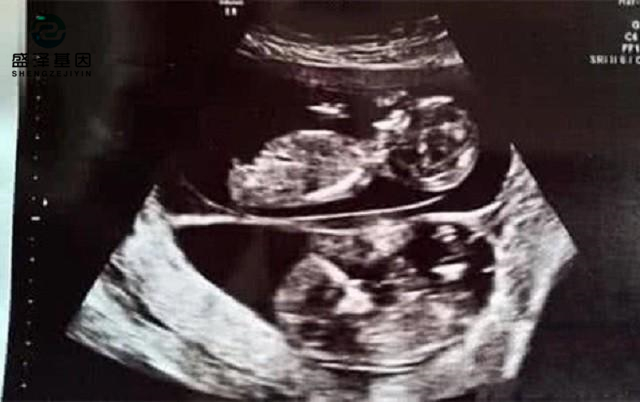

親子鑒定師講述:老公明明是無精癥,老婆卻試管嬰兒懷孕成功?

一個離奇的親子鑒定故事……此刻,呈現給你有個女的跟老公做了3次試管嬰兒,失敗了兩次,第三次卻意外成功。剛驗出來懷孕的時候,... -